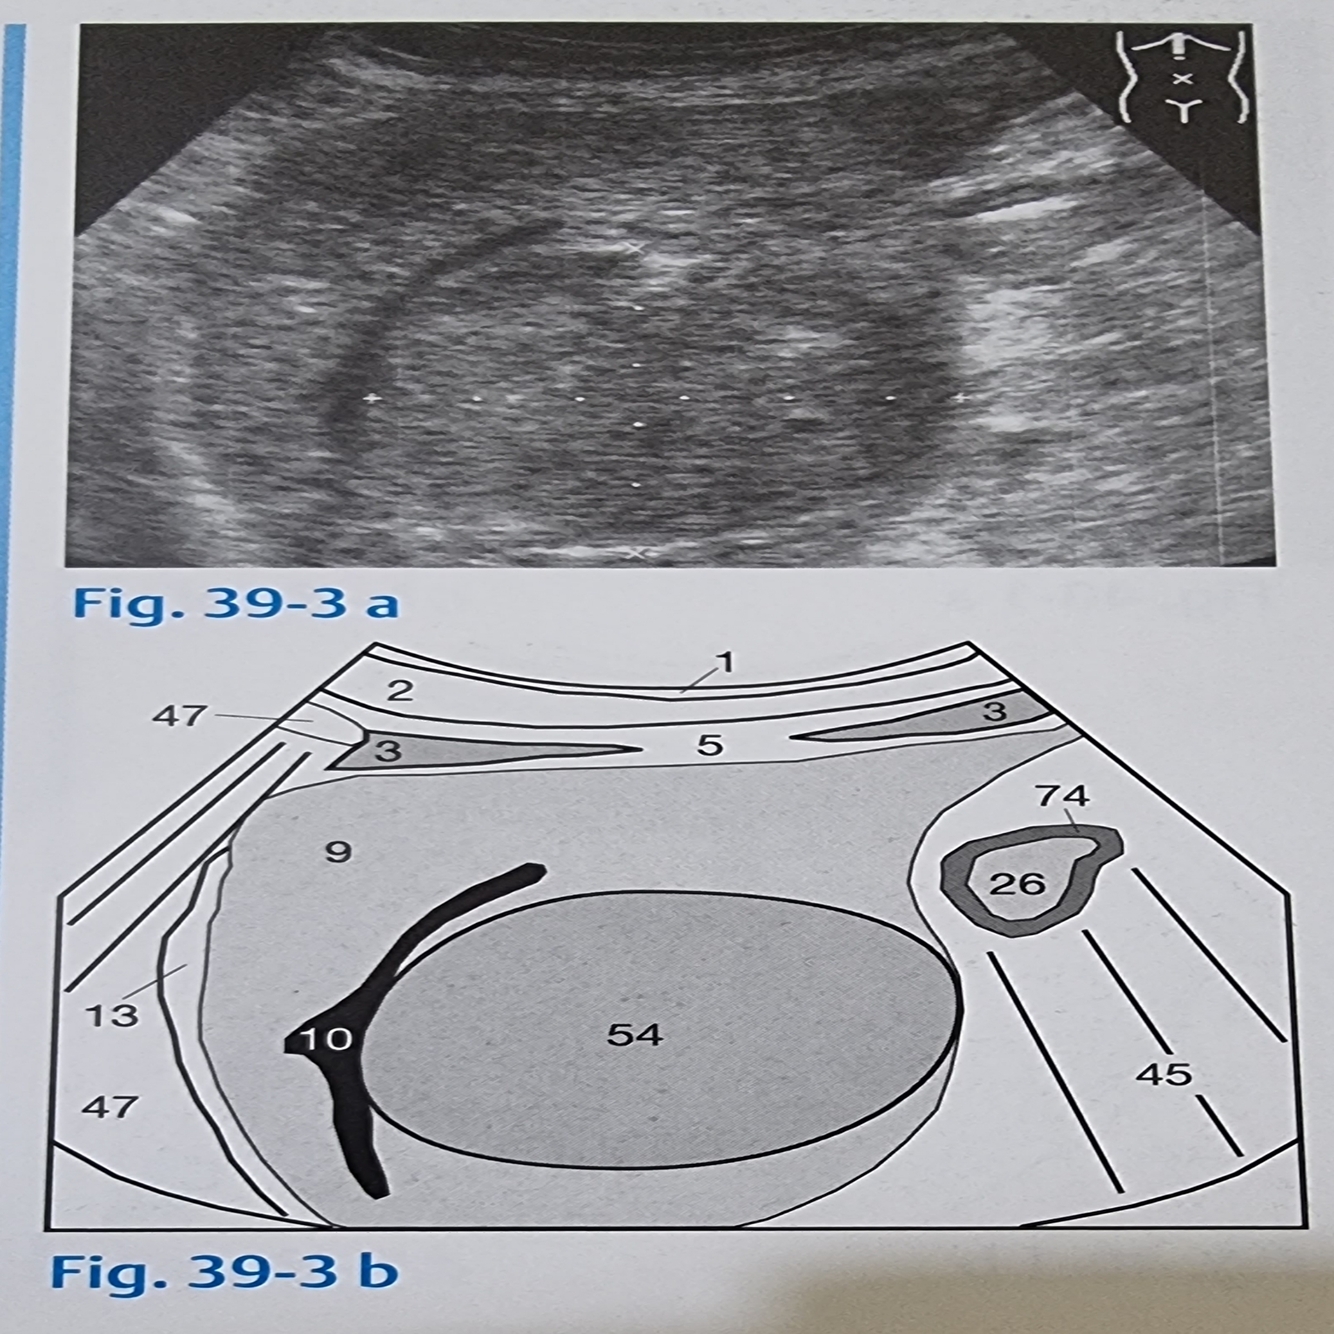

19

Q

Tumores hepáticos podem ser reconhecidos como?

A

Por sinais indiretos como o deslocamento em forma de arco das veias vizinhas

Veia hepática (10)

Tumor (54)

20

Segmentação hepática

Desenhe mentalmente